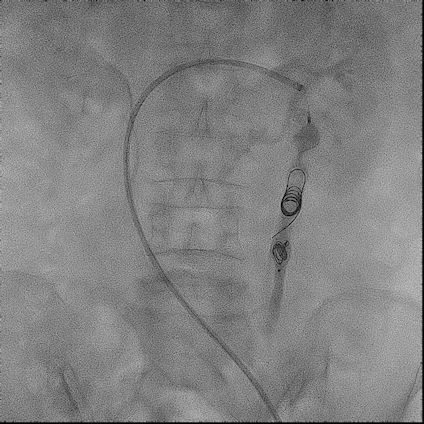

手术过程(一):

超选左肾静脉,左侧卵巢静脉,造影见卵巢静脉曲张明显,直径13 mm,盆腔大量曲张静脉显影。

图片